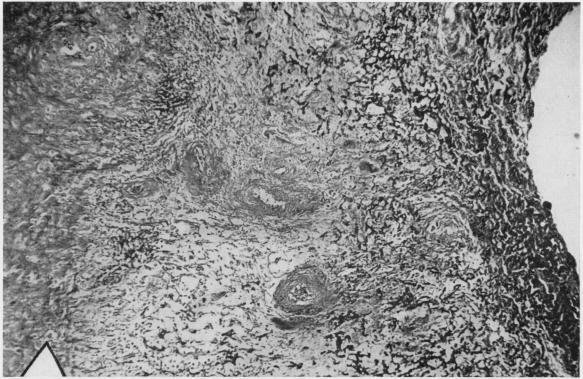

ULTRAMICROSCOPIC STRUCTURE OF THE RHEUMATOID NODULE.

Ann Rheum Dis. 1964 Sep;23(5):345-63. doi: 10.1136/ard.23.5.345.